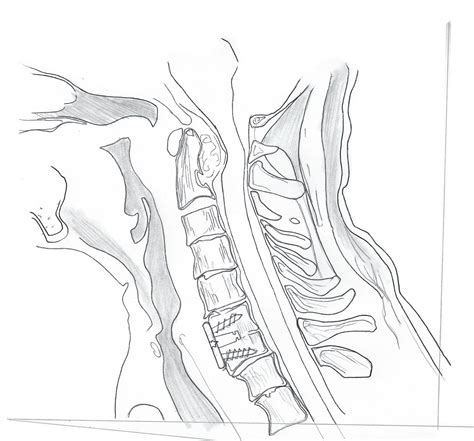

The human neck is marvelously designed with a natural, inward-curving arc known as the cervical lordosis. This gentle "C" shape is essential for supporting the weight of your head, acting as a shock absorber, and facilitating a full range of motion. However, modern lifestyle factors—ranging from prolonged screen time to poor posture—have led to an increasing prevalence of a straight cervical spine. Often referred to as "military neck" or cervical kyphosis in severe cases, the loss of this natural curvature can lead to a cascade of musculoskeletal issues. Understanding the causes, symptoms, and corrective measures for this condition is vital for anyone looking to maintain long-term neck health and spinal integrity.

In a healthy neck, the cervical vertebrae align in a lordotic curve that distributes the load of your head evenly across the spine. When you have a straight cervical spine, this curvature flattens out, causing the neck to appear straight when viewed from the side on an X-ray or MRI. When this curve is lost, the weight of your head is no longer balanced, placing excessive stress on the muscles, ligaments, and intervertebral discs. This biomechanical imbalance is the root cause of many chronic neck pain complaints.

Manual adjustments and traction therapies can help mobilize restricted spinal segments. Certain specialized forms of spinal remodeling are specifically designed to address the straight cervical spine by gently applying pressure to restore the curvature.